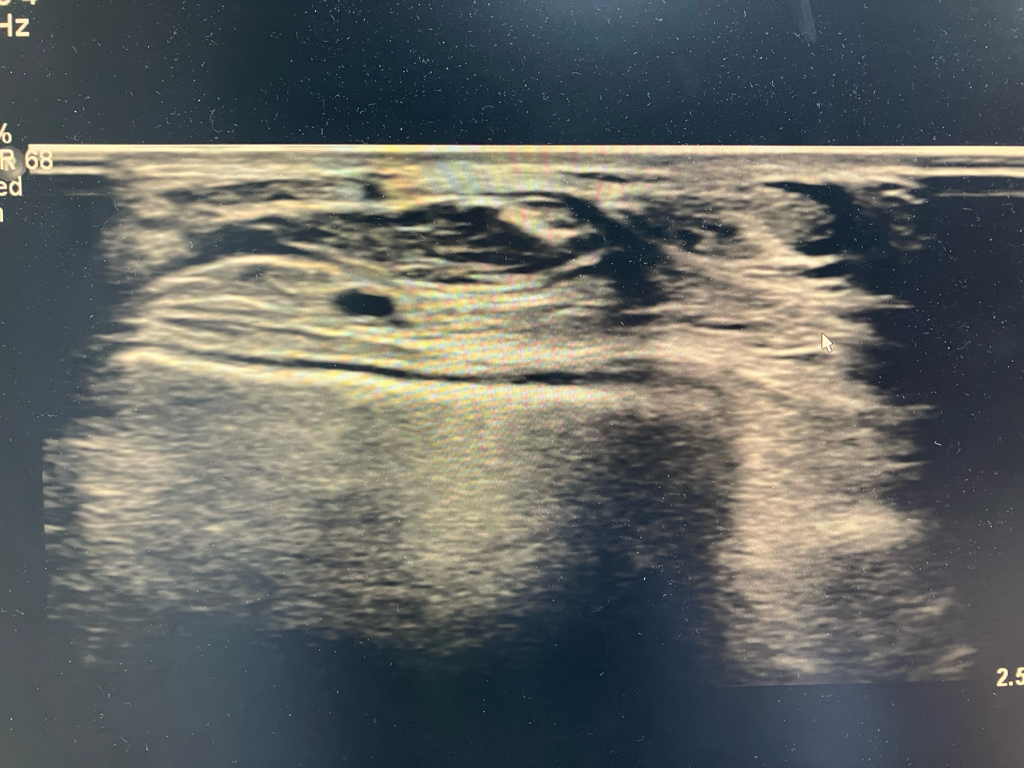

초음파는 이렇게 찍어놓은것만 보고 판단하기 어렵고 실시간으로 보면서 판단을 해야합니다.